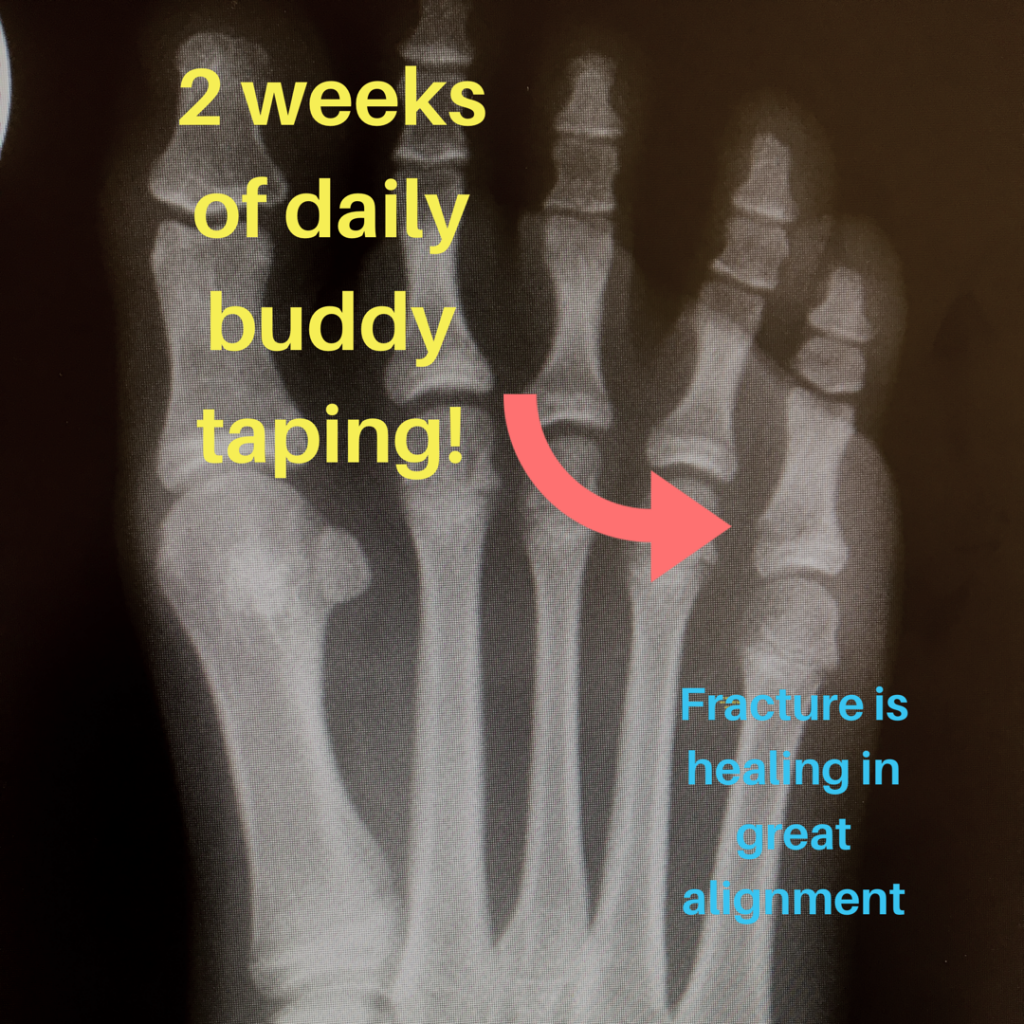

From www.drjenniferkern.com

A Broken Toe and the Buddy Taping Method Buddy Tape Metacarpal Fracture is buddy taping as effective as plaster immobilization for adults with an uncomplicated neck of fifth metacarpal. despite evidence showing that buddy taping the fourth and fifth digits together yields. We compare buddy taping with plaster casting for uncomplicated fifth metacarpal (boxer's) fractures. adult patients with acute fifth metacarpal neck fractures with less than 70º volar angulation. Buddy Tape Metacarpal Fracture.